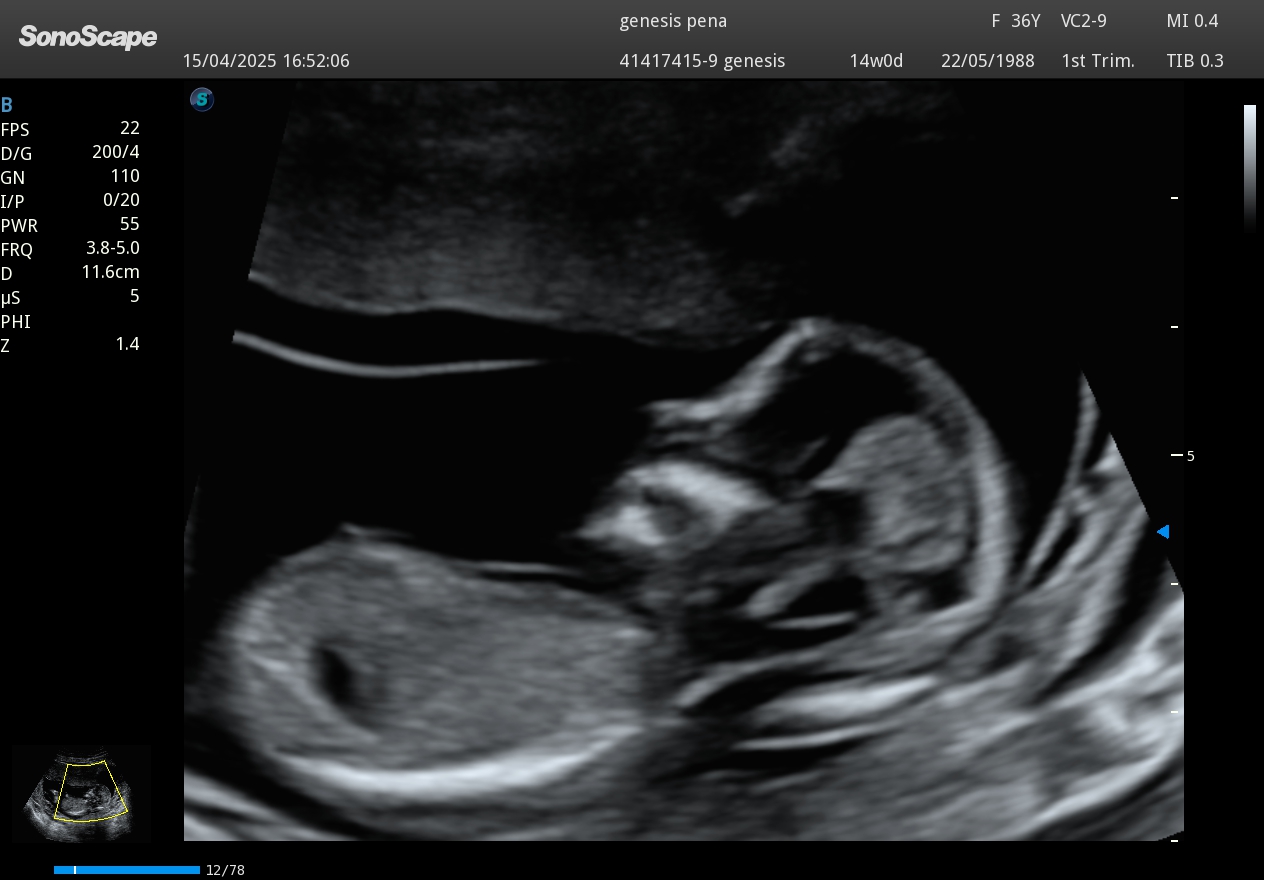

Perfil fetal en ecografía Doppler obstétrica 2D

Imagen real de perfil fetal captada mediante Ecografía Doppler 2D.